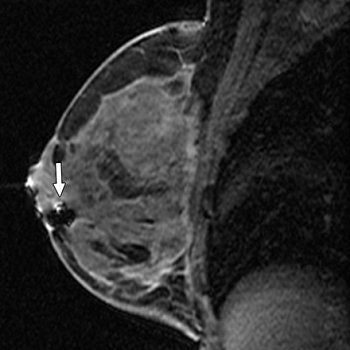

| Same patient as above. Sagittal T1-weighted MR image after needle localization shows signal void from placement of three MRI-compatible bracketing wires (arrows) to assist surgeon in wide excision. Histologic analysis revealed extensive multifocal ductal carcinoma in situ (DCIS), micropapillary, flat (clinging), and focally solid types, intermediate nuclear grade, arising in background of atypical ductal hyperplasia, with multiple positive margins. Mastectomy was performed, yielding residual DCIS with negative sentinel nodes. Lee J, Kaplan JB, Murray MP, Bartella L, Morris EA, Joo S, Dershaw DD, Liberman L, "Imaging-Histologic Discordance at MRI-Guided 9-Gauge Vacuum-Assisted Breast Biopsy" (AJR 2007; 189:852-859). |